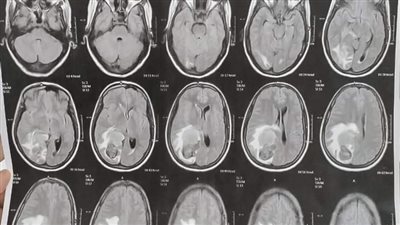

نجاح جراحة نادرة لوحمة دموية بالمخ بمستشفى العصبية والنفسية بجامعة أسيوط

في إنجاز جديد يضاف إلى سلسلة الإنجازات الطبية التي تحققها مستشفيات جامعة أسيوط، نجح فريق طبي بمستشفى الأمراض العصبية والنفسية وجراحة المخ والأعصاب في إجراء عملية جراحية نادرة لمريضة تعاني من وحمة دموية كبيرة بالمخ، تحت رعاية الدكتور أحمد المنشاوي رئيس الجامعة، والدكتور علاء عطية عميد كلية الطب ورئيس